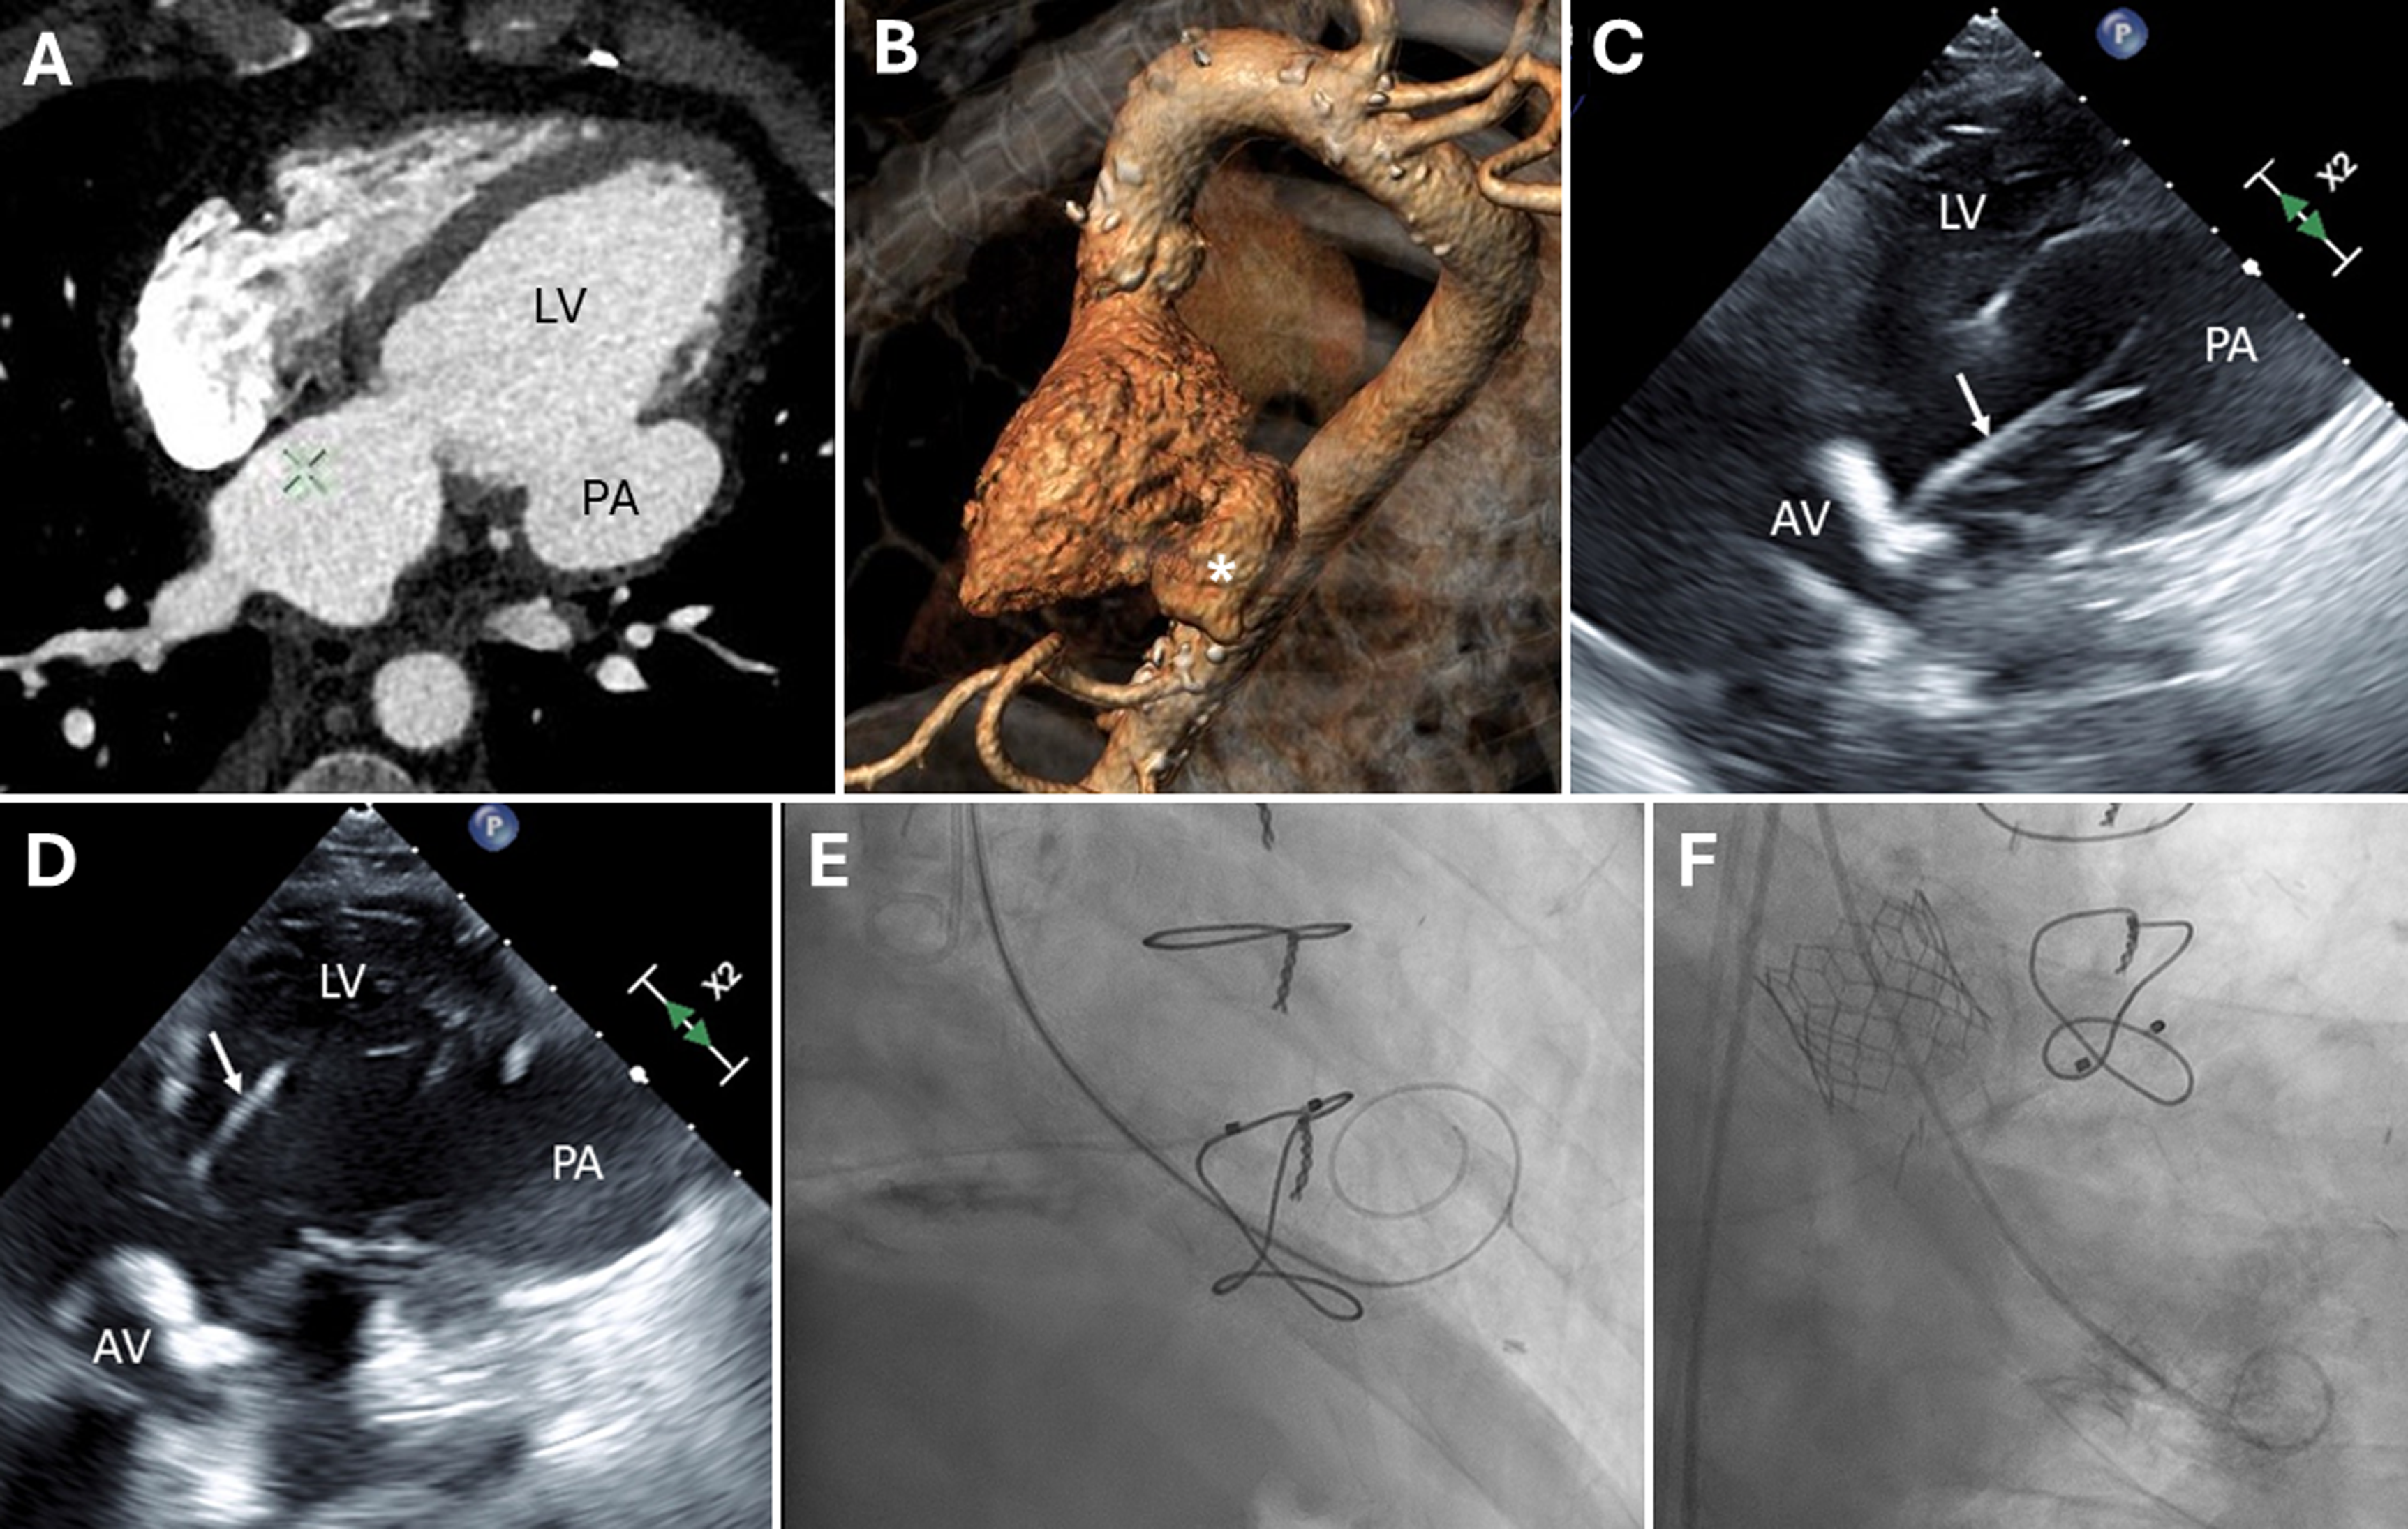

An 85-year-old man with a history of myocardial infarction and coronary bypass surgery presented with severe symptomatic aortic stenosis. Echocardiography revealed pressure gradients of 73/40 mm Hg across the aortic valve, an aortic valve area of 0.74 cm2, and a 35% ejection fraction. The left ventricular (LV) posterior wall was akinetic, with a large lateral wall pseudoaneurysm. Computed tomography angiography confirmed a large basal lateral left ventricular (LV) pseudoaneurysm (4.9 x 4.7 x 4.5 cm) (Figure 1A and B). The patient was at high risk for surgical valve replacement and was referred for a transcatheter aortic valve replacement (TAVR). We were concerned that inadvertent insertion of a stiff guidewire into the pseudoaneurysm during TAVR would cause cardiac rupture.

TAVR was performed under general anesthesia with transesophageal echocardiography (TEE) guidance. Initial positioning of a straight-tip guidewire within the pseudoaneurysm (Figure 1C) was detected by TEE and the wire was repositioned to the LV apex (Figure 1D). A stiff pre-shaped guidewire (Confida, Medtronic) was then positioned within the LV apex (Figure 1E) and direct implantation of a 26-mm Sapien 3 valve (Edwards) was performed successfully (Figure 1F). The patient recovered uneventfully. This case emphasizes the importance of multi-modality pre- and intra-procedural imaging during TAVR.